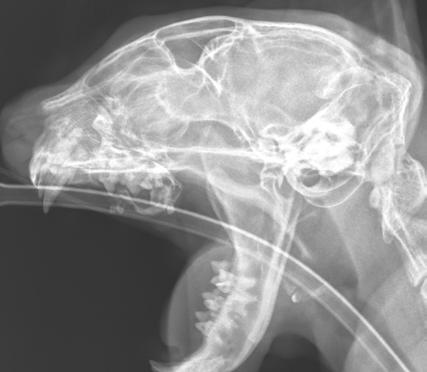

An 8-month-old female desexed Labrador retriever cross presented for a 4–6-week duration of left forelimb lameness.

On clinical exam, there was mild pain on manipulation of both shoulder joints.

Q. What is your radiological diagnosis?